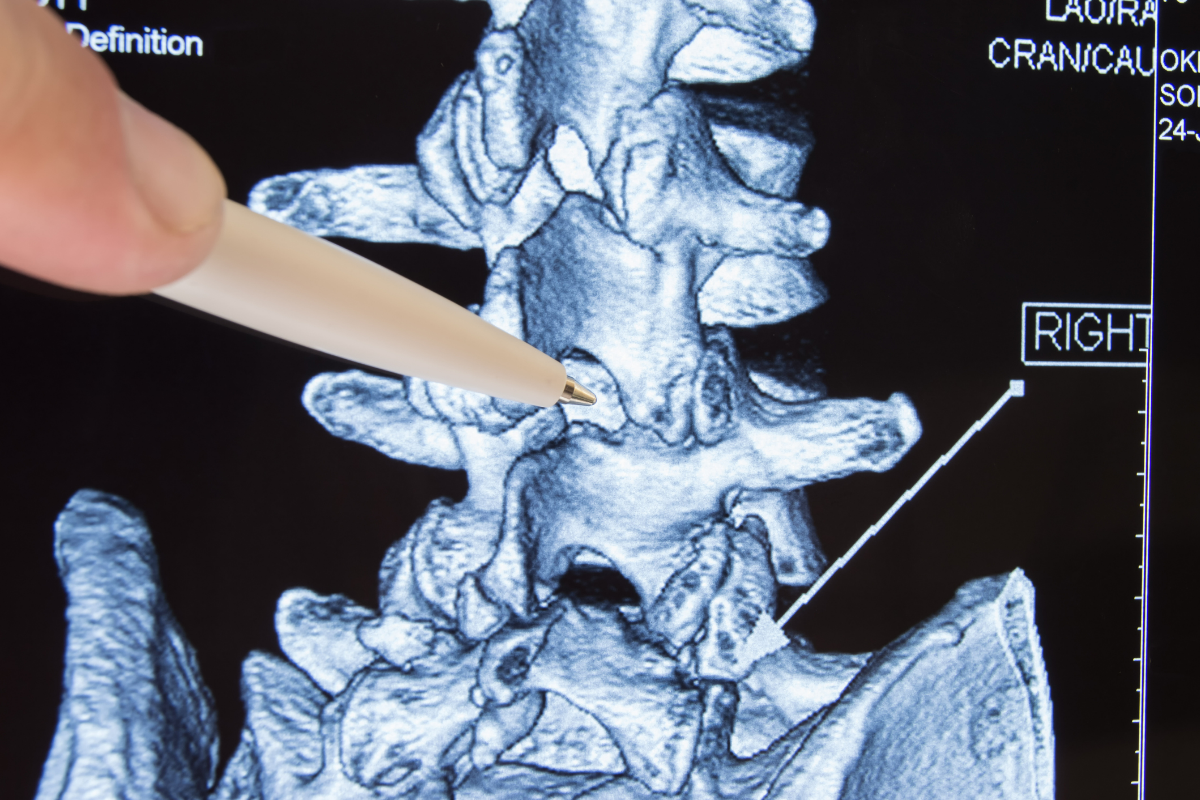

Spinal fusion is considered complex because it involves joining two or more vertebrae together to stabilize the spine, limiting its motion. This surgical procedure is used to treat various spinal conditions that may lead to instability or abnormal curvature. Spinal fusion may be used for degenerative disc disease, scoliosis, spinal stenosis (spinal canal narrowing) and other conditions.

Laminectomy is a type of surgery in which a surgeon removes part or all of the vertebral bone (lamina). This helps ease pressure on the spinal cord or the nerve roots that may be caused by injury, herniated disk, narrowing of the canal (spinal stenosis) or tumors.